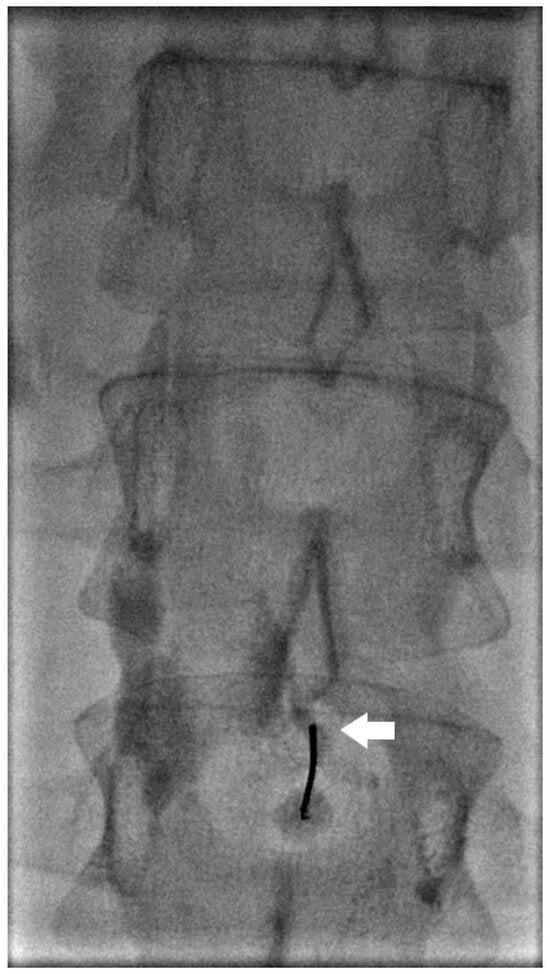

Kaminski et al. compared lymphangiography only versus lymphangiography and embolization. The median amount of iodized oil (lipidol) used was 12 mL (range 8–20 mL) with 20 mL used in all cases of lymphangiography only. Embolization of the target lymph vessel was performed with coils and/or liquid embolics (Histoacryl) diluted with ratio 1:1–1:5. Coils were used in the embolization of large lymph vessels to prevent distal migration of glue to the venous system (Figure 3 and Figure 4). Glue-only embolization was performed in peripheral lymphatics with no risk of glue migration or lymph node embolization. When embolization was not feasible, interstitial lymph node embolization was performed. Dietary restriction with Medium Chain Triglyceride supplement was prescribed for 2–3 days post-procedure. Embolization achieved 26/28 (92.9%) and 11/12 (91.7%) clinical success in traumatic and non-traumatic thoracic chylous effusion, respectively; lymphangiography only achieved 1/2 (50.0%) and 1/6 (16.7%) in traumatic and non-traumatic thoracic chylous effusion, respectively. Clinical success in combined abdominothoracic chylous effusion was achieved in 2/3 (66.7%) and 0/5 (0.0%) of embolization and lymphangiography only patients, respectively. Overall success of thoracic intervention was 39/48 (81.3%) with a significant difference between traumatic and non-traumatic groups. Complications were seen after lymphatic embolization in 5 patients with one grade 1, two grade 2, one grade 3, and one grade 4 as follows: pulmonary glue migration, upper extremity vein thrombosis, edematous pancreatitis, bleeding from branch of left hepatic artery, biliary peritonitis [22].

Figure 4. Spot image from the same patient in Figure 3 showing lipiodol within the thoracic duct (arrow) and coils at the distal thoracic duct (arrowhead) to address a leak in the mediastinum (star).